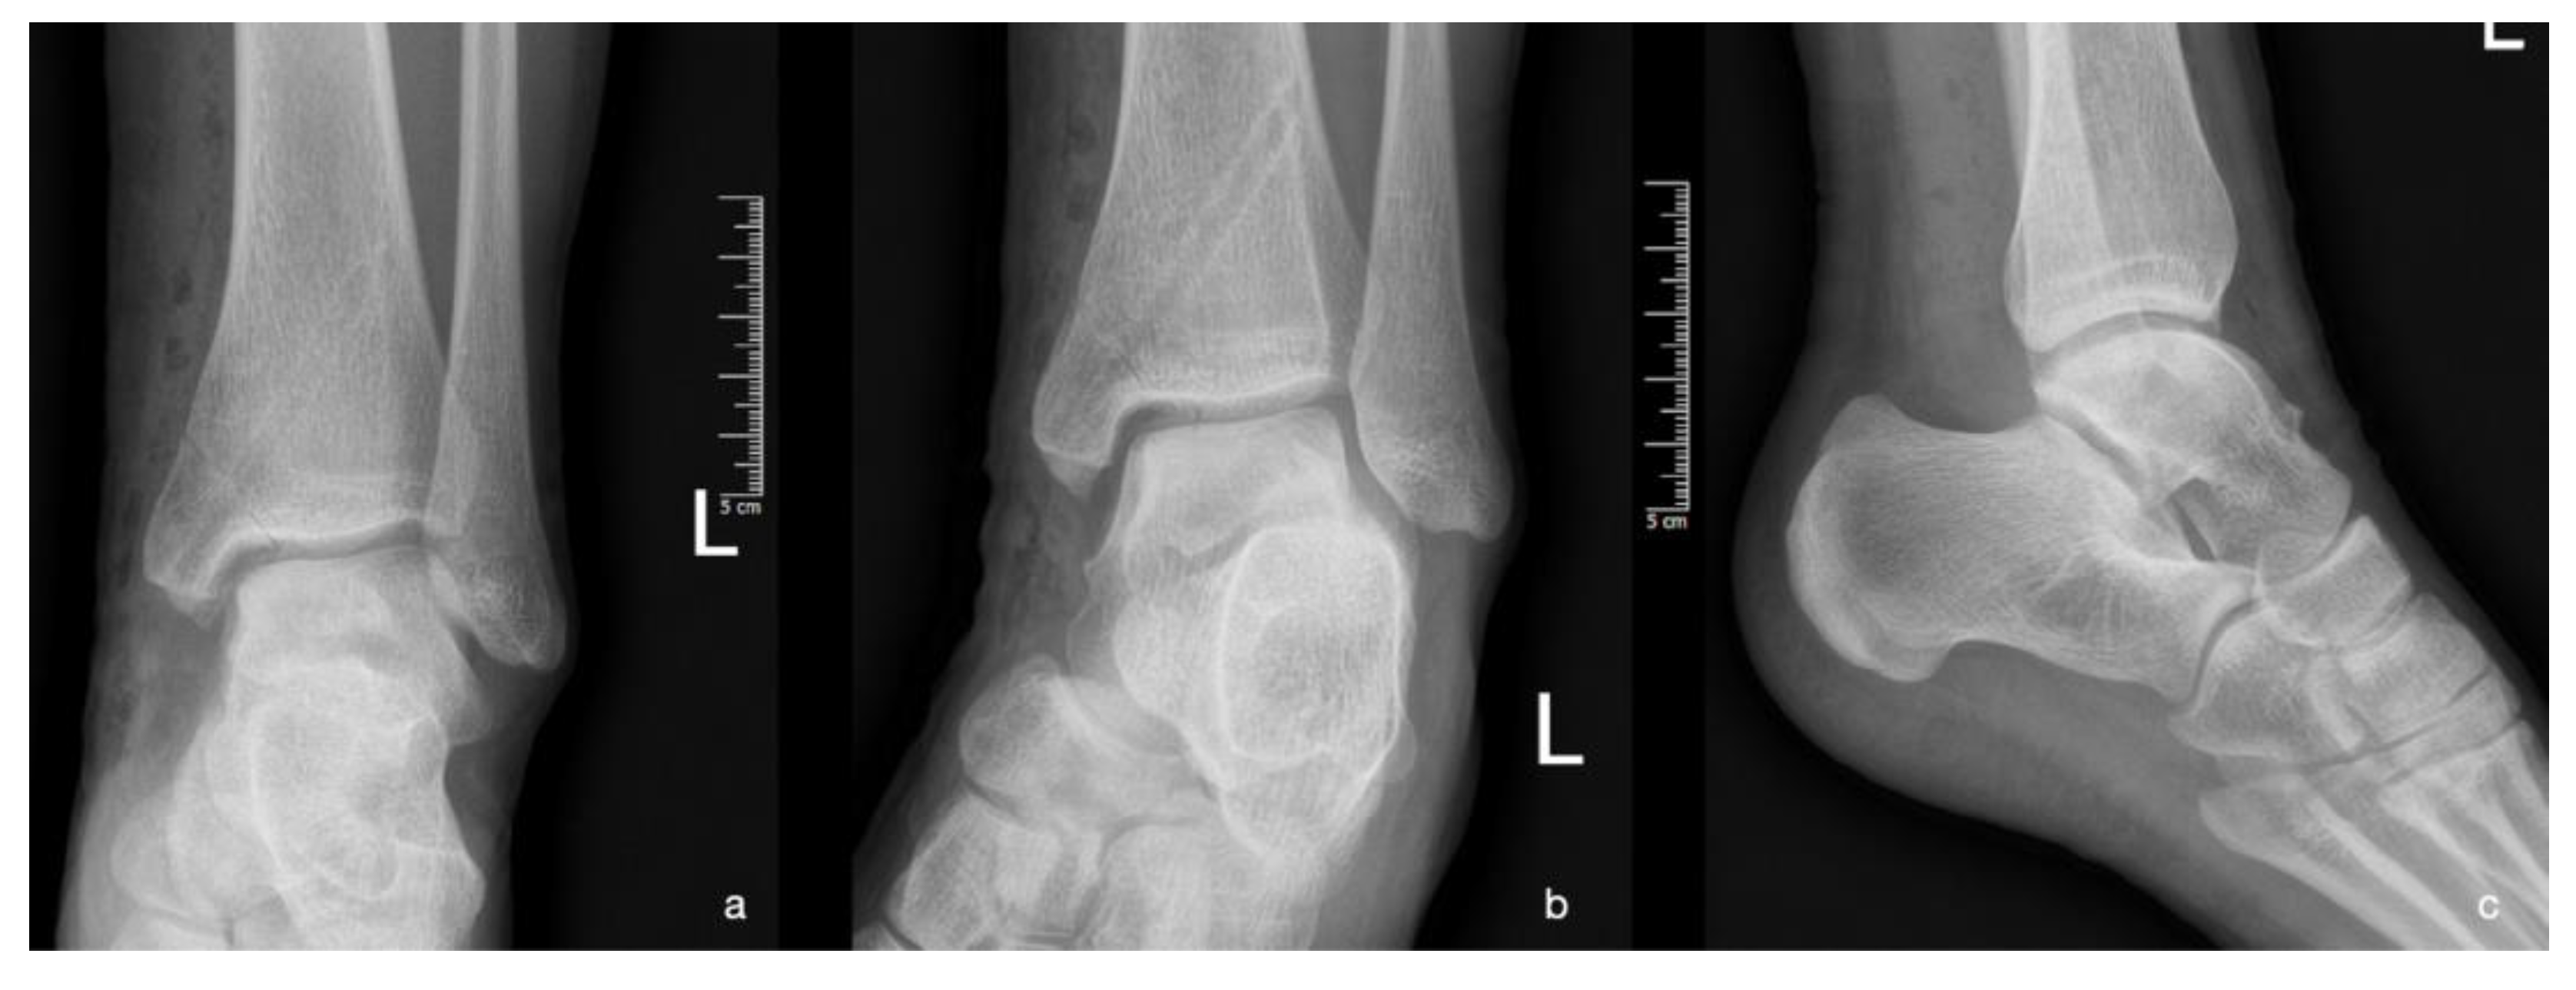

| Stage 1 | Small subchondral compression | Intact Lesion | A stable lesion of the softened area covered by intact cartilage. | Thickening of articular cartilage and low signal changes | Small change of signal, without clear fragment margins. | Epiphyseal cartilage lesion with necrotic center |

| Stage 2 | Partially detached osteochondral fragment | A lesion with signs of early separation | Lesions with partial discontinuity which are stable when probed | Articular cartilage has been breached with a low signal rim behind the fragment indicating fibrous attachment | OSteochondral fragment with clear margins, without fluid in between | Epiphyseal cartilage lesion with complete or incomplete rim calcification |

| Stage 3 | Completely detached, non-displaced | Partially detached lesion | Lesions with complete discontinuity which are not dislocated (Dead in situ) | High signal changes behind the fragment indicate synovial fluid between the fragment and the underlying subchondral bone | Fluid is visible partially between the fragment and bone | Partially or completely ossified lesion |

| Stage 4 | Completely detached and displaced - loose body | Craters with loose bodies (salvageable or non-salvageable) | Empty defect bed with loose or dislocated fragment | Loose body | Fluid surrounds the fragment but it is still in situ | A healed osseous lesion with scar |

| Stage 5 | Scranton and McDermott modification : Subchondral Cyst | - | - | - | The fragment is completely detached and displaced | Unhealed, detached osseous lesion (Sequestrum) |